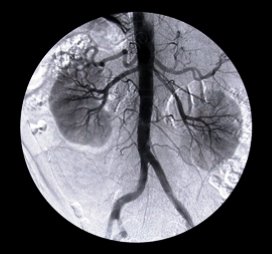

Een 60-jarige man met een myocardinfarct in de voorgeschiedenis, ondergaat een open nefrectomie (nierverwijdering) links. De patiënt krijgt